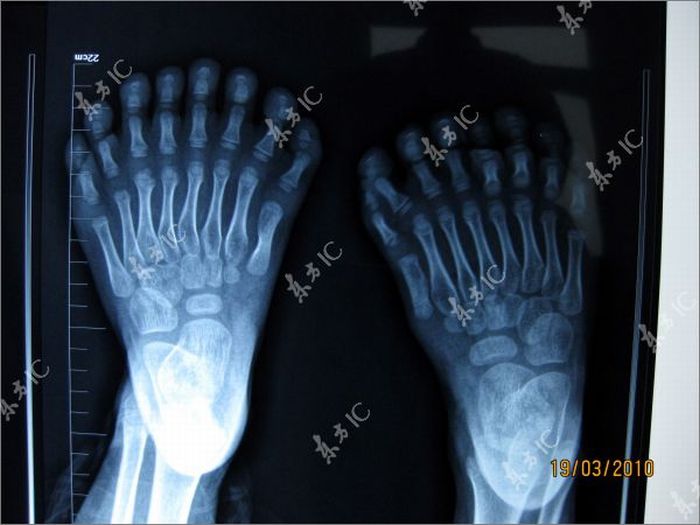

This Chinese boy has 34 fingers.Now he has to undergo a surgery to remove extra fingers.The previous world record was 25 fingers.